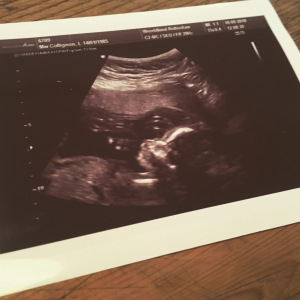

De taalnazi kwam met een kater uit zijn nest, ik had lekker uitgeslapen en mijn zus had de middag vrij genomen om gezellig mee te gaan. Het zou een ontspannen uitje worden. Maar toen ik daar op die tafel lag met een koude kwak gel op mijn pens, was het toch… anders. Shit got real. Ik was klaarblijkelijk vergeten dat het belangrijkste gedeelte van de twintigwekenecho is: ontdekken of alles goed is met je kleine monstertje.

De mevrouw die de echo deed, kenden we niet. Ze stelde zich stug voor, met een wel hele zuinige glimlach. Ze had kort, grijs haar, een strenge bril en ze nam haar vak uiterst serieus. Ik vond haar zeer zakelijk, alsof ze geen emotionele band met ons op wilden bouwen (en ik snapte ineens ook de reden: want wie weet wat voor verschrikkelijk nieuws ze zo meteen gaat vertellen…). We mochten absoluut niet denken dat dit een pretecho was (stiekem verlangde ik wel naar de alienachtige substantie die ik zo fel had afgewezen). Secuur ging het kortharige ijskonijn elk lichaamsdeel van de baby af. ‘Het ene beentje, met het voetje, de knie.’ Ze zei er verder niets bij. Ze erkende de aanwezigheid van een knie of het hartje of de darmpjes. Het was niets meer dan een ordinaire afvinklijst waarvan ik steeds ongeruster werd of het monstertje wel helemaal compleet was aangeleverd. God, straks mist het een been. Of een hand. Of een milt. Kun je zonder milt? Of alvleesklier. Hebben ze nu al een alvleesklier? Ik werd er bloednerveus van.

Aan het einde van de echo vroeg ze of we het geslacht wilden weten.

‘Dit is het schaambeen,’ zei het konijn toen.

Daar moesten we iets uit opmaken. Mijn zus begon te glimmen. Ik zag er nog niets in. Ik was naast semi-opgelucht ook nog in semi-shock.

‘Het is een meisje,’ zei het konijn koeltjes.